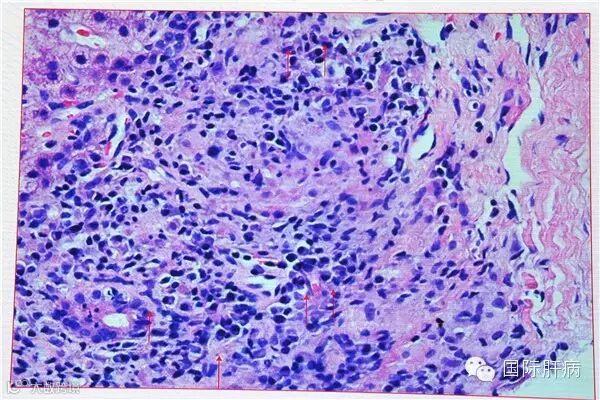

4)淋巴细胞穿入现象

穿入现象是指淋巴细胞进入肝细胞胞浆的组织学表现,多见于活动性界面炎区域。我国研究表明,65%的AIH患者可见穿入现象,显著高于其他慢性肝病患者,并与AIH肝内炎症和纤维化程度相关;穿入的淋巴细胞主要为CD8+T细胞,可导致肝细胞凋亡。

淋巴细胞穿入(HE,400倍)